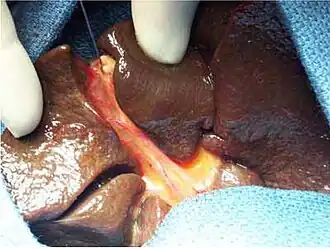

Операцию желательно производить не позже чем над двухмесячными детьми, поскольку положительные результаты операции может уничтожить развивающийся цирроз печени, резко снижающий процент выживаемости. В настоящее время широко используются реконструктивные операции (процедура Касаи, по имени предложившего её японского хирурга), при своевременном выполнении которых положительный прогноз ожидается у 30-40 % детей. При отсутствии эффекта или невозможности реконструктивной операции (например, нарушения внутрипеченочных протоков) показано проведение трансплантации печени.